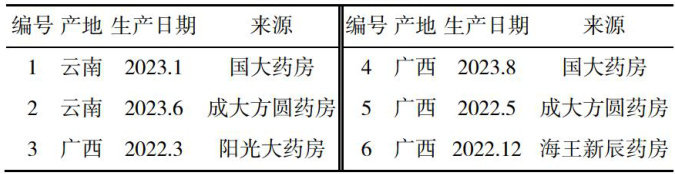

科学研究 | 高液相色谱法同时测定番泻叶中芦荟大黄素和大黄酸的含量

科学研究 | 高液相色谱法同时测定番泻叶中芦荟大黄素和大黄酸的含量